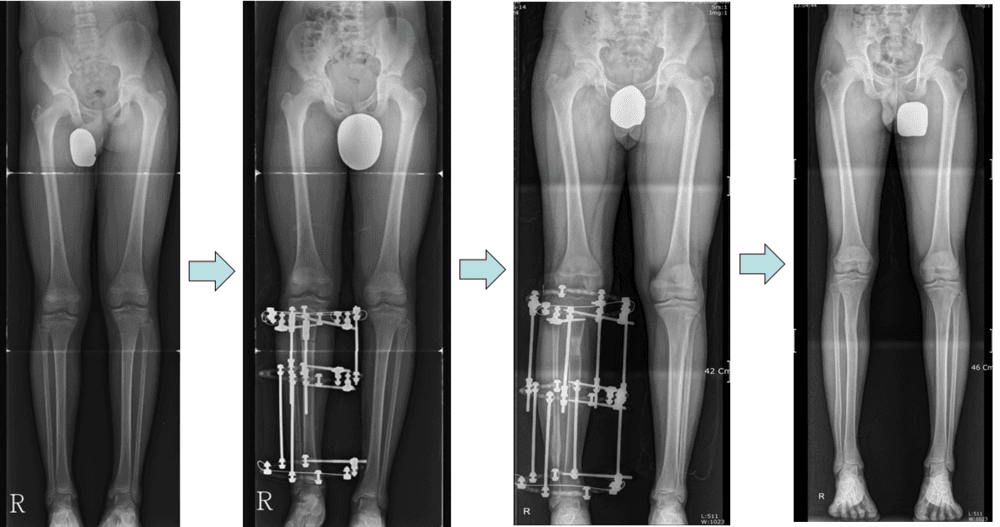

저신장증에서 하지연장